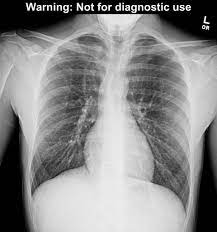

This website is designed primarily as an educational resource. Consult a doctor for medical advice. Catamenial pneumothorax is a condition of air leaking into the pleural space occurring in conjunction with menstrual periods (catamenial refers to menstruation), and or during ovulation, caused by the abnormal growth of endometrial tissue in the membrane surrounding the lung and diaphragm. Oct 09, 2019 · pneumothorax or a collapsed lung, is a lung condition in which the lung(s) has been injured by infection, trauma, disease, cigarette smoking, and other medical problems. Jul 23, 2021 · pneumothorax (collapsed lung) is an injury to the lung that causes air or gas to build up in the thin layer of tissue that covers the lungs and lines the interior wall of the chest cavity. Doctors treat a pneumothorax or collapsed lung depending upon the cause. A pneumothorax can develop into a collapsed lung. It is not intended to provide medical advice on personal health matters or to guide treatment — which is only appropriately done by a qualified health professional. Pneumothorax can lead to a collapsed or punctured lung. It typically happens when there is a rupture of a small air sac on the outside of the lung. This air pushes on the outside of your lung and makes it collapse. Ultrasound imaging also may be used to identify a pneumothorax. This is when the punctured lung occurs without any exact cause. Depending on the cause of the pneumothorax, a second goal may be to prevent recurrences. Ultrasound imaging also may be used to identify a pneumothorax. Jul 23, 2021 · pneumothorax (collapsed lung) is an injury to the lung that causes air or gas to build up in the thin layer of tissue that covers the lungs and lines the interior wall of the chest cavity. A pneumothorax can be caused by: A pneumothorax can develop into a collapsed lung. Pneumothorax Pulmonary Disorders Merck Manuals Professional Edition Pneumothorax Pulmonary Disorders Merck Manuals Professional Edition from www.merckmanuals.com

A pneumothorax can develop into a collapsed lung. Jul 23, 2021 · pneumothorax (collapsed lung) is an injury to the lung that causes air or gas to build up in the thin layer of tissue that covers the lungs and lines the interior wall of the chest cavity. Pneumothorax Imaging Practice Essentials Radiography Computed Tomography Source: img.medscapestatic.com

A pneumothorax can develop into a collapsed lung. Depending on the cause of the pneumothorax, a second goal may be to prevent recurrences. Pneumothorax Pulmonary Disorders Merck Manuals Professional Edition Source: www.merckmanuals.com